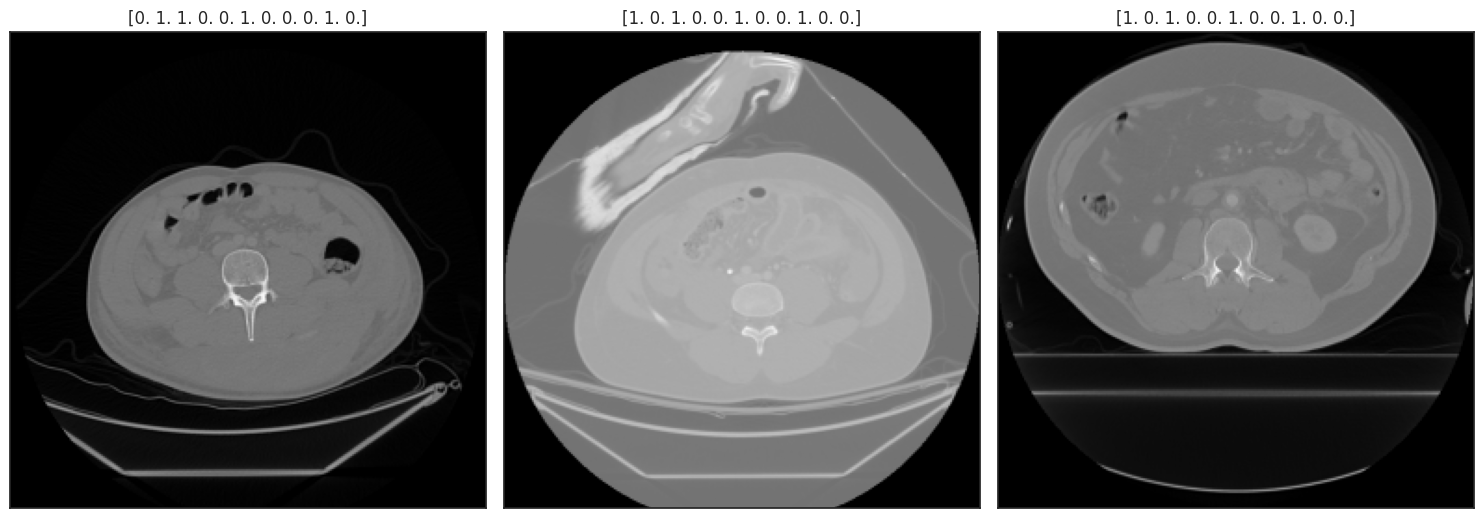

RNSA 2023 Abdominal Trauma Detection